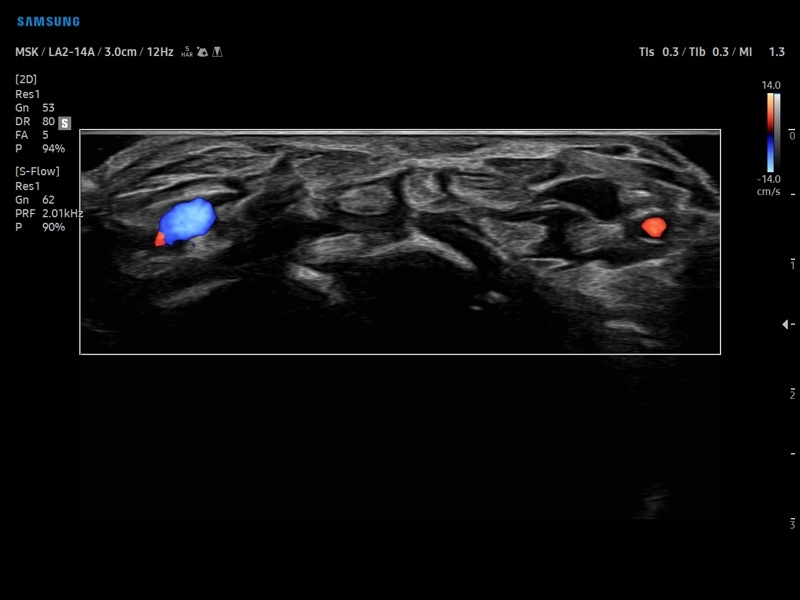

• Диагностика костно-мышечной системы

• Технологии визуализации: MV Flow, LumiFlow, SEE Stream, Panoramic

• Модуль MV-Flow – программа (режим), позволяющая визуализировать кровоток в микроциркуляторном русле с высоким разрешением без использования контраста.

• Модуль NerveTrack – автоматическое определение срединного нерва в поперечном сечении с использованием искуственного интеллекта.